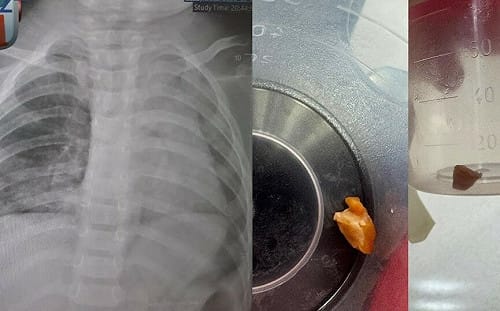

1歲娃肺塌陷險死!元兇竟是「阿嬤的花生」 醫曝2小時搏命救援內幕